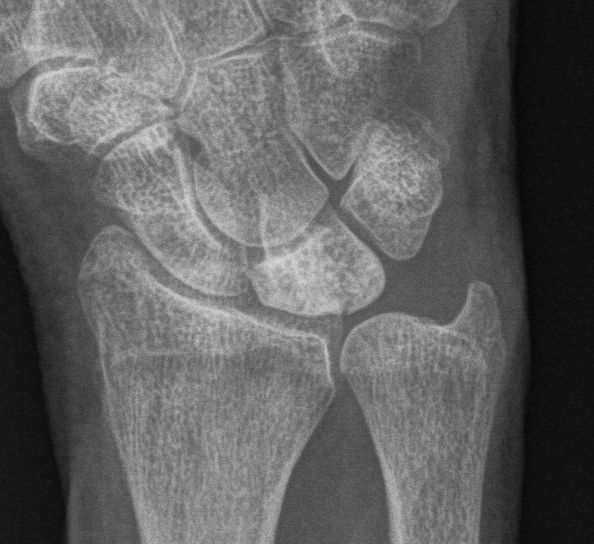

Xray

Progressive changes of AVN

- sclerosis

- fragmentation / fracture / flattenging

- midcarpal collapse: scaphoid flexion / capitate descent

- radiocarpal and midcarpal osteoarthritis

Lichtmann Classification

Stage I

- xray normal

- diagnosed on MRI

Stage II Stage IIIA

Sclerosis

Collapse / fragmentation

Normal carpal height

Kienbocks Kienbocks

Stage IIIB Stage IV

Scaphoid flexed / Capitate migrates proximally

Pancarpal osteoarthritis